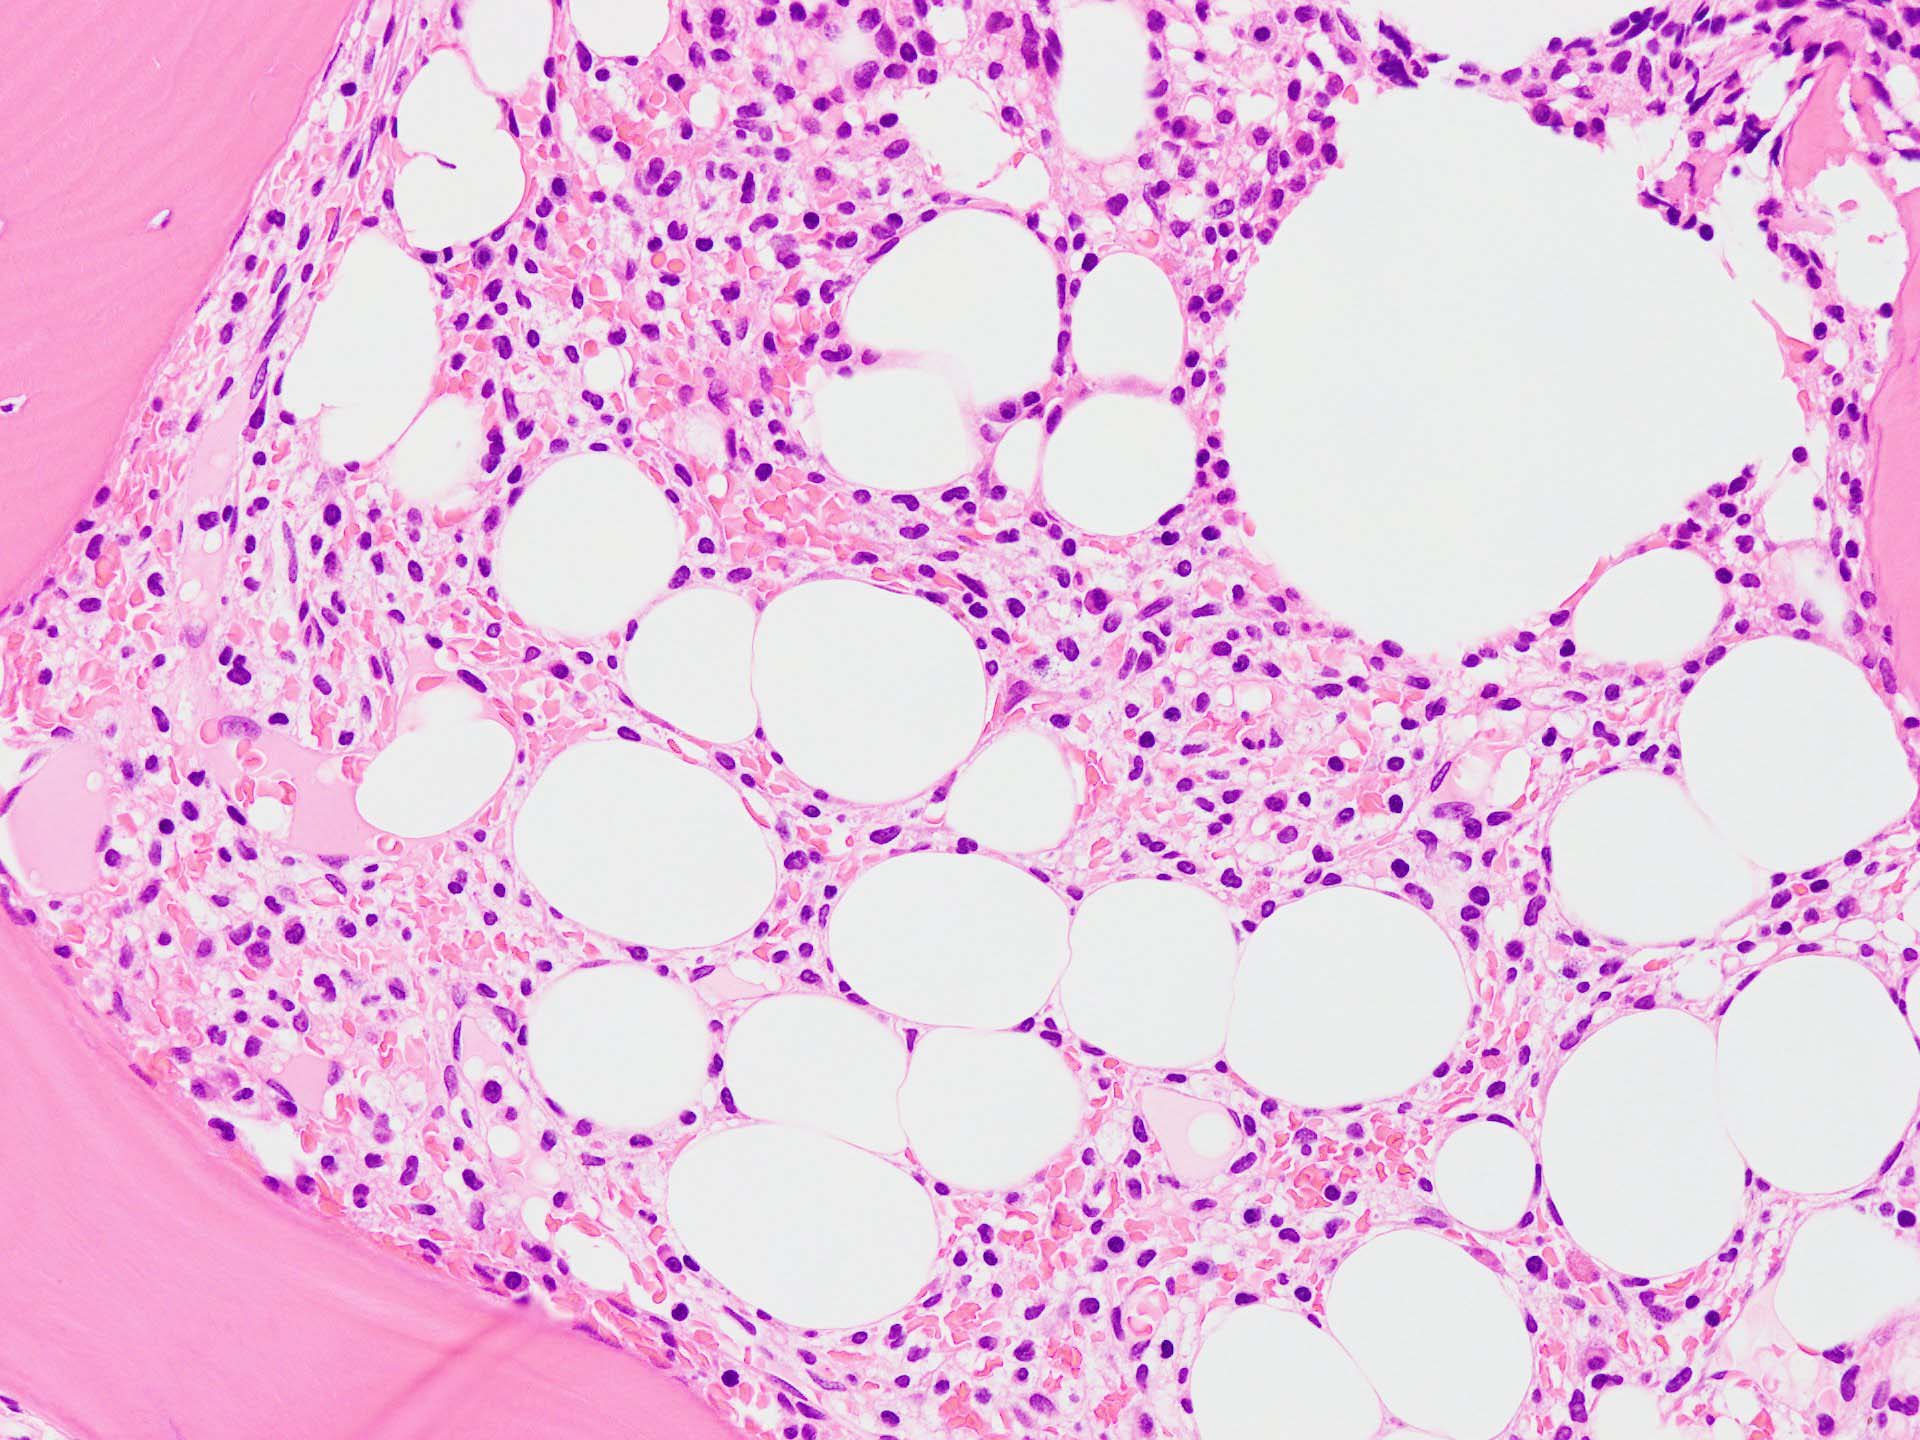

骨髄生検

bone marrow trephine biopsy: dry tapのため骨髄生検が行われる. cellularityは40-80%とhypercellular marrow. 流れのある細胞配列は線維化を疑わせる.

ASD-Giemsa陰性の細胞がシート状に増殖する. 核はクロマチン濃染, 核小体は不明瞭.類円形, 卵円形, くびれを持つ多稜形核, 長円形いびつで屈曲した核, など多彩. 細胞質は淡清色調, 広く淡明. 赤芽球血島は幼若赤芽球のみで形成される異形成像を示す. やや離れて成熟赤芽球が疎な集簇を示す.

Ag染色では, 疎な弾性線維が増生し,増殖細胞を小胞巣状に分画するいわゆる「lymphomatoid pattern」を呈する. 本例では, Mgkに異形成所見がある.